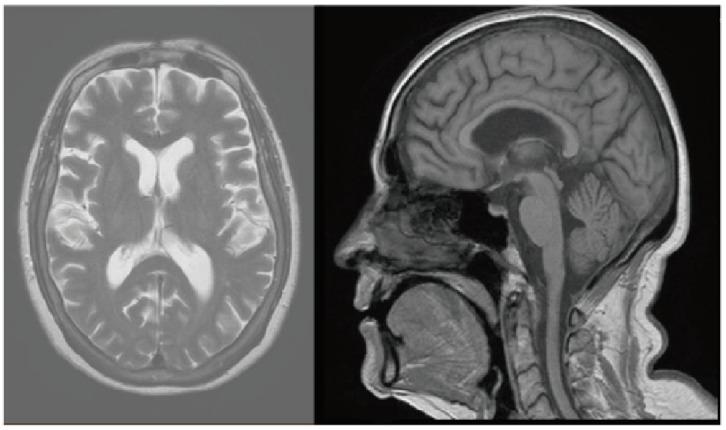

The introduction of immune checkpoint inhibitors (ICIs) has revolutionized cancer treatment standards and significantly enhanced patient prognoses. However, the utilization of these groundbreaking therapies has led to the observation and reporting of various types of adverse events, commonly known as immune-related adverse events (irAEs). In the following article, we present four patients who encountered uncommon toxicities induced by ICIs. The first patient was a 59-year-old female diagnosed with stage 4 lung adenocarcinoma. She received immunotherapy (pembrolizumab) together with chemotherapy and subsequently developed autonomic neuropathy (AN). The next two patients also received chemo-immunotherapy (pembrolizumab) and were both 63-year-old males with stage 4 lung adenocarcinoma. One of the two experienced palmoplantar keratoderma, while the other presented with Reiter's syndrome (urethritis, conjunctivitis and arthritis). The 4th patient, an 80-year-old male with stage 4 squamous cell carcinoma of the lung, received chemo-immunotherapy (pembrolizumab) and developed myasthenia gravis.